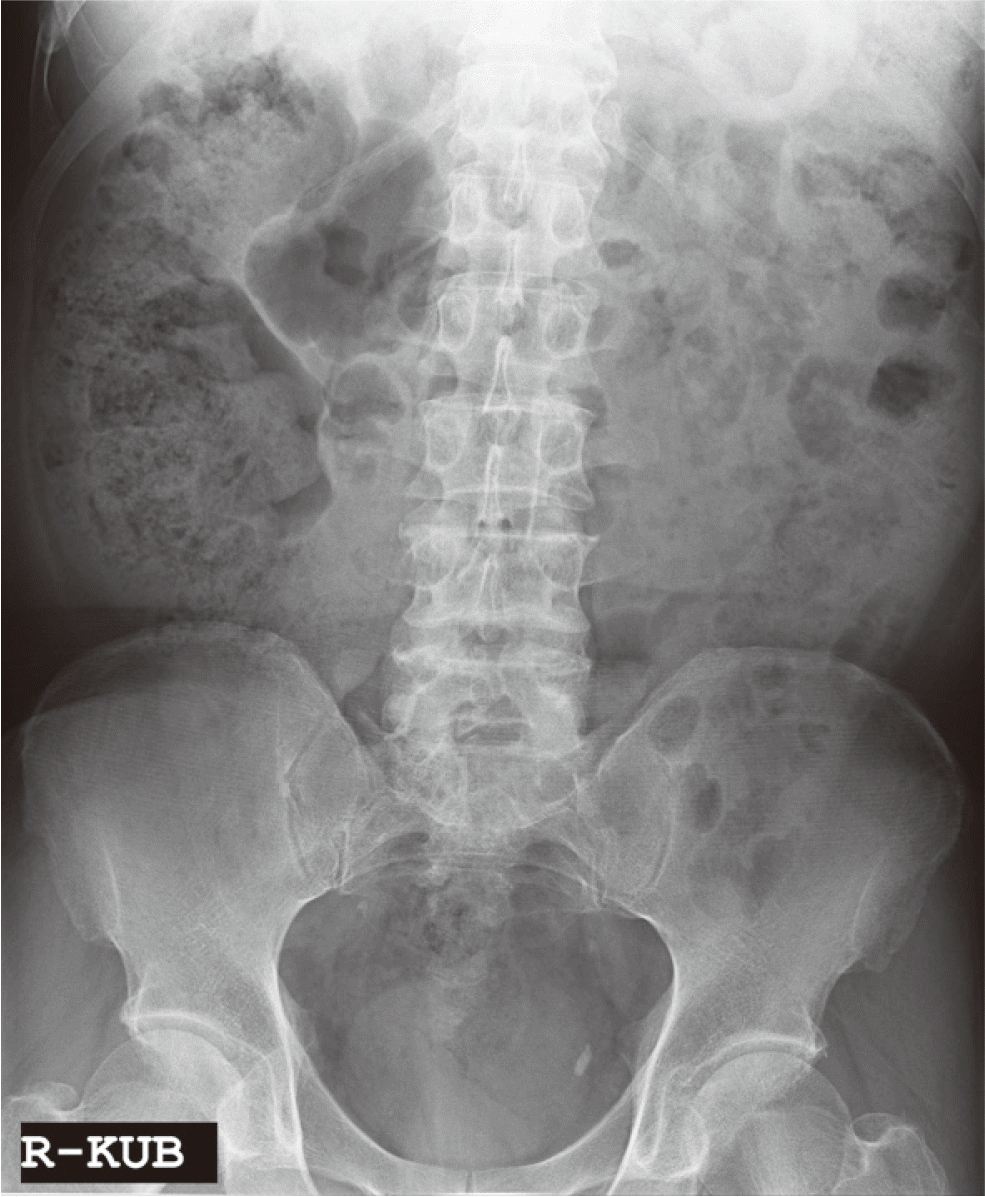

60세 남자 환자로 전체적인 치과치료를 위해 본원에 내원하였다. 환자는 의과적으로 기질성 정신장애를 진단을 받았으며, 거동이 불편하고 보행이 불가능하여 요양병원에서 입원 치료 중이었다. 정신건강의학과에서 환자의 정신장애에 대해 치료상태가 안정된 상태임을 확인한 후, 치과치료를 진행하였다. 파노라마 방사선 사진 및 구강검사에서 상악 우측 제1소구치와 제1대구치, 좌측 제제1, 2소구치, 하악 우측 제1대구치에 잔존 치근이 존재하였으며, 상악 우측 견치와 하악 좌측 견치 및 소구치에서 치아우식증이 관찰되었다(Fig. 1). 환자의 의과적 병력과 치료의 협조도, 구강위생 조절 능력 등을 고려했을 때, 가철성 보철물의 유지와 관리가 어렵다고 판단되어 고정성 보철물로 수복을 계획하였다. 예후가 불량한 상악 우측 견치, 제1소구치, 제1대구치와 좌측 제제1, 2소구치, 하악 좌측 견치, 제1소구치와 우측 1대구치를 발치 한 후, 치아 상실부위에 임플란트 식립을 하였고(Fig. 2), 골유착 기간을 거쳐 최종인상을 채득하였다. 제작한 임플란트 보철물을 장착하던 과정에서 치과의사는 하악 우측 제제1, 2소구치와 제1대구치로 이루어진 3본 지르코니아 보철물이 환자의 구강 내로 떨어뜨렸고, 떨어진 즉시 환자의 두부를 좌측으로 돌려 환자가 보철물을 삼키지 않도록 노력하였으나, 환자가 보철물을 삼키게 되었다. 환자가 보철물을 삼킨 이후 기침이나 구토 반사 등의 특이적 소견을 보이지 않았으며, 호흡상태는 양호하였다. 환자 보호자에게 보철물 장착과정에서 보철물을 구강 내로 떨어뜨렸고, 이후 삼킴이 발생하였음을 설명하였다. 그리고 삼켜진 보철물의 위치 확인을 위하여 인근 내과로 전원 의뢰를 시행하였다. 전원 의뢰된 당일, 내과에서 복부 방사선 사진을 촬영하였고, 판독 결과 보철물이 위장에 위치를 하고 있음을 확인하였다. 24시간 이후 배출될 것으로 예상되어 48시간 후 재촬영이 필요할 것이라는 회신서를 확인하였다(Fig. 3). 2일 후 환자를 내원하도록 하여 추가로 복부 방사선 사진을 촬영하였다. 방사선 사진에서 위장관 내에서 보철물 확인되었다. 환자의 거동이 불편하여 위장관 운동이 저하되어 있는 상태이기 때문에 배출이 지연될 수 있다는 의과적 소견을 회신 받았다(Fig. 4). 8일 후 환자의 복부 방사선 사진을 촬영하였으며, 보철물이 위장관에서 완전히 배출되어 체 내에 있지 않음을 확인하였다(Fig. 5). 이 후 하악 우측 제1, 2소구치와 제1대구치에 새로운 보철물을 제작하여 최종 합착(Rely-X, 3M ESPE, St Paul, USA)을 시행하였다(Fig. 6).